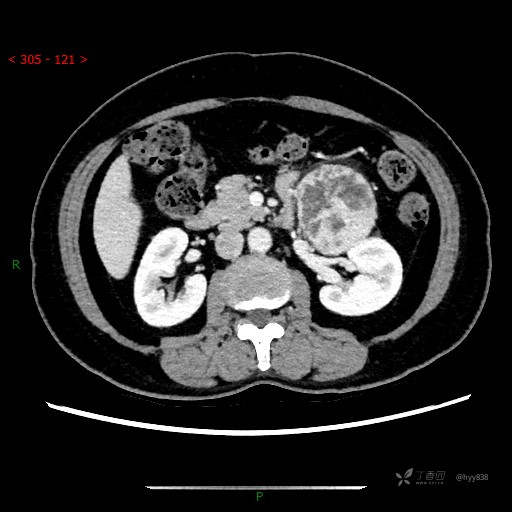

中腹部CT平扫

增强动脉期

增强静脉期